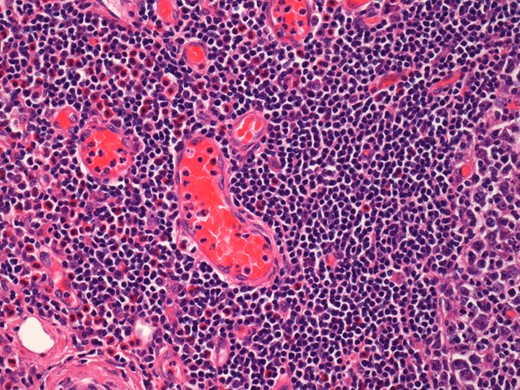

On histological examination the lymph node tissue demonstrated preserved normal architecture. Capsular fibrosis and follicular hyperplasia was noted. The secondary follicles showed polarized germinal centres with tingible body macrophages and well defined mantle zones. The paracortex was expanded by a mixed chronic inflammatory cell infiltrate. Scattered eosinophils were also observed. The parotid parenchyma was mostly replaced by a diffuse lymphoid infiltrate. The residual parotid gland showed lymphoid aggregates in a periductal location. The lymphoid component demonstrated prominent follicular hyperplasia and well developed mantle zones. Parafollicular expansion by an eosinophil-rich mixed inflammatory cell infiltrate was present. Prominent hyalinization of the sinusoidal vessels with thick collagen bundles within the surrounding stroma was also observed. Eosinophil clumps were seen in areas, infiltrating the follicle locally (Figs 5 and 6).

Histological examination of the parotid gland demonstrating diffuse lymphoid infiltrate with prominent follicular hyperplasia and well developed mantle zones (haematoxylin and eosin stain, ×2.5).